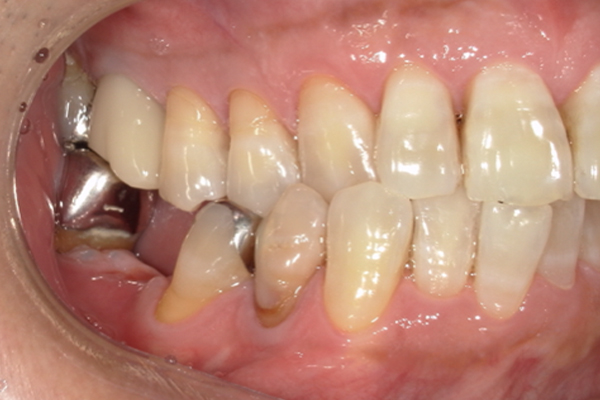

| 主訴 | 歯が痛い |

|---|---|

| 治療内容 | 右上奥歯に対するインプラント治療 (今後右下に対してもインプラント治療を予定) |

| 治療期間 | 6ヶ月 |

| 治療費 | 44万5千円 |

| 治療 リスク | インプラントを埋入したあと3ヶ月程度待ち時間が必要。 その期間は仮歯を使用していただきます。 |